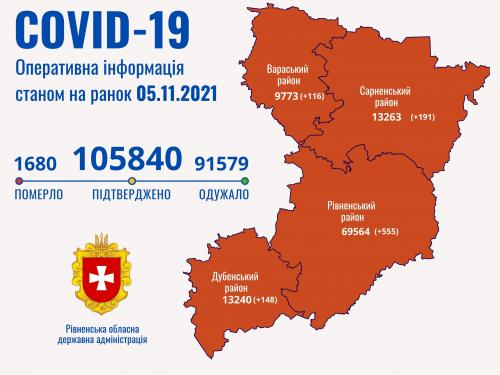

Пів тисячі - у важкому стані, 9 жителів Рівненщини померли за добу від коронавірусу